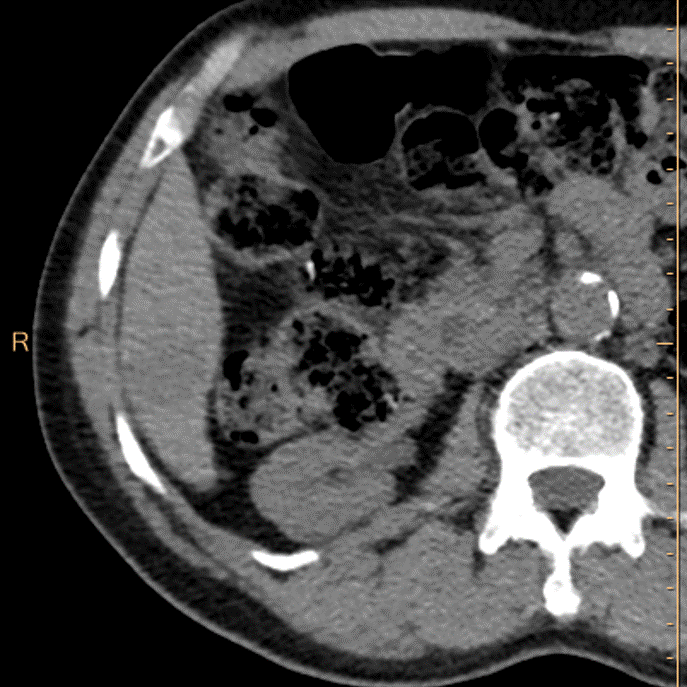

Portal venous phase, conventional phase. You cannot assess for washout, which is one of the major criteria for LiRADS.

Portal venous phase, 40 keV mono-E. The washout is obvious!

PVP, electron density weighted image. See the lesion very well. Not sure this represents washout, as EDW seems to reflect non-contrast image quite well.